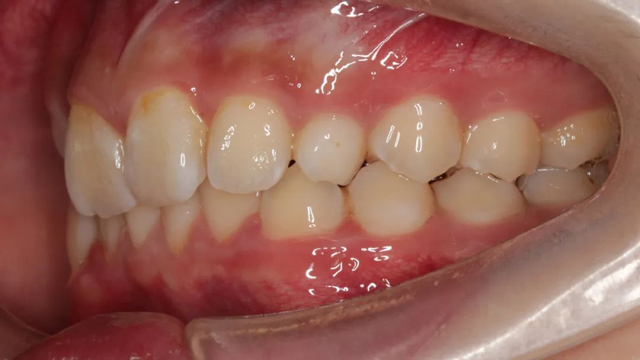

2021年8月(矯正前口內照)

這位小患者的口腔問題包括:牙列不齊,個別門牙反頜,左上尖牙完全埋伏阻生,另外,CBCT顯示右上門牙牙根腭側內還有一顆多生牙。

簡單地說,牙齒不整齊只是小問題,他更大的問題是:在不該長牙的地方多長了一顆牙,而乳尖牙滯留,早該替換出來的尖牙長不出來,這兩顆牙的問題如果不及時干預治療,會帶來很多長期的口腔問題。